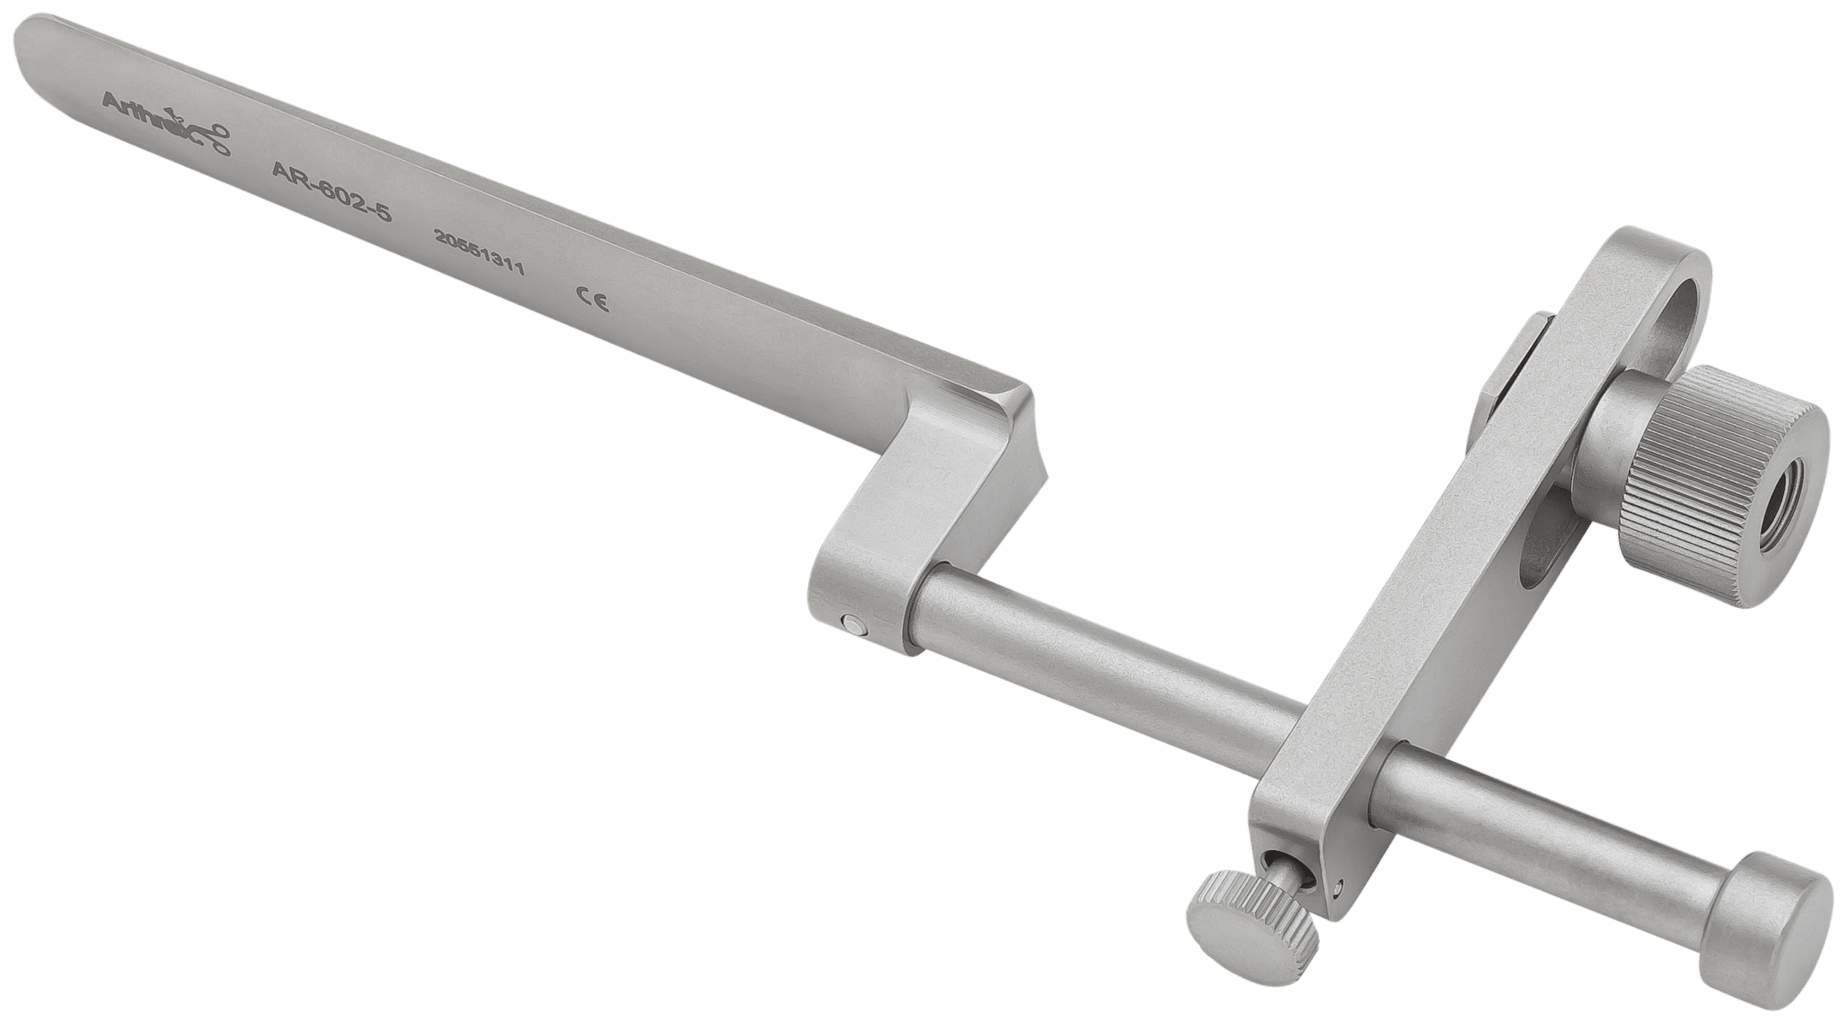

Orthodontic News - OrthoFXTM Announces Nationwide。Orthodontic Aligners: Current Perspectives for the Modern。What's New in Aligners for 2024 | Orthodontic Products。Full article: Clear aligners generations and orthodontic。。「アライナージェネレーション Alignergeneration : Dr. 尾島賢治のテクニック&分析ポイント131のすべて」尾島賢治 / 檀 知里 / 渡邉仁資 / 熊谷友理子定価: ¥29,700(税込)